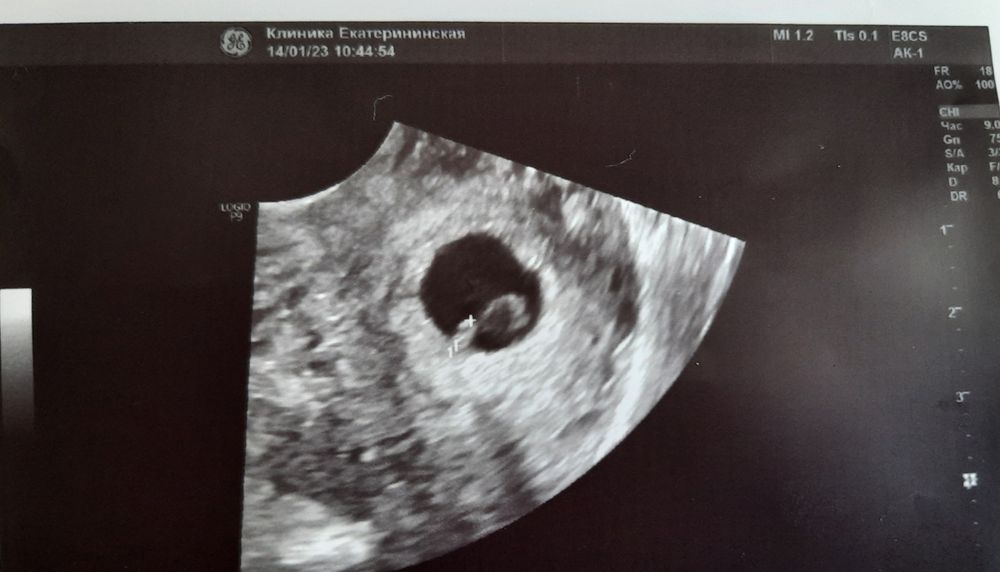

При полной терапии Клексана, Утрожестана, Эутирокса, Метипреда и витамин я проходила еще почти 2 недели и просо не выдержала ! Не дождалась назначенной даты 20.03 а поехала 16 числа к своему врачу предварительно сдав утром хгч в последний раз. Анализ пришел раньше чем я доехала до места- 2400 ! В Узи надобность отпала сама собой((( При сроке по первому дню кд в 44 дня или почти 7 недель это было ни что… Узи по итогу конечно сделали для подтверждения зб и пя оказалось пустым... как сейчас помню- кругленькая черная точка размером с куриное яйцо как мне виделось, но на деле пя было всего 15мм, и в нем пустота...непроглядная темень... Копии не сохранилось, так как я ее разорвала прям там в кабинете. Это моя вторая беременность и я прекрасно знала как должна выглядеть в норме картинка на этой неделе... Жм тоже был на всех узи, по моему мм 4, но через 3 дня когда был назначен день таблетированого ма и мы сделали ещё одно контрольное узи- исчез и он((( 19 марта я выпила первые таблетки для ма ! Конец !

Вот мой эмбрион, а говорили анэмбрионию. Я понимаю что замер, но диагноз неверный сказали, а при хорошем аппарате увидели.